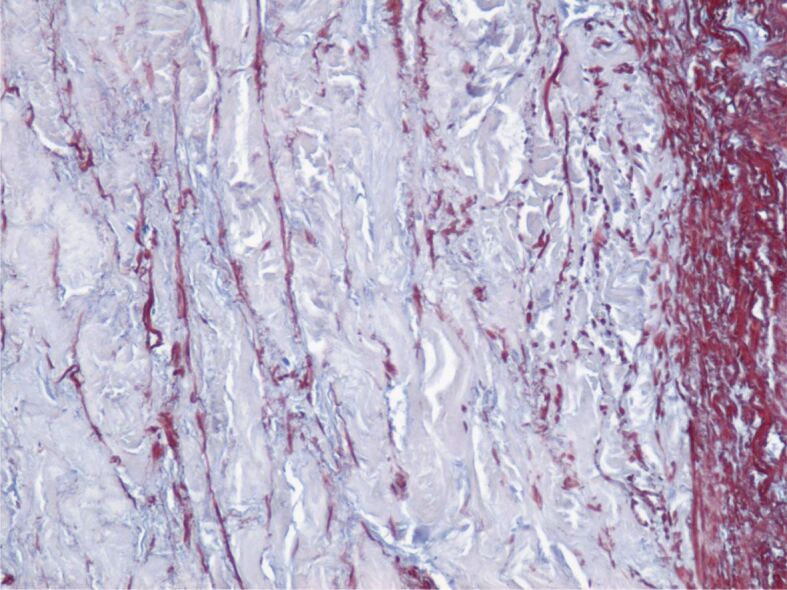

动脉瘤的定义是动脉壁扩张,直径超过相关血管正常直径的 1.5 倍。主动脉瘤(AA)可发生在任何部位,但大多位于腹部和肾下部,并延伸至髂动脉。主动脉瘤通常没有症状,最常见的情况是在对其他疾病进行各种成像检查时偶然发现。AA 的破裂通常很剧烈,是导致心脏性猝死的原因之一。手术治疗以及最近的血管内治疗是修复 AA 的唯一有效方法。在这项研究中,我们对有冠状动脉造影指征的稳定型劳累性心绞痛患者进行了 AA 诊断筛查。研究于 2021-2023 年期间在罗马尼亚蒂米什瓦拉心血管疾病研究所进行。在需要进行冠状动脉造影的 2458 名劳累性心绞痛患者中,有 1844 名患者(75%)至少有一个动脉粥样斑块狭窄,其中 312 名患者有 AA,其中 173 名患者位于腹主动脉水平。

An aneurysm is defined as a dilation of the arterial wall with a diameter exceeding 1.5 times the normal diameter of the vessel concerned. Aortic aneurysms (AAs) can develop at any level but are mostly found at the abdominal and infrarenal levels and extend to the iliac arteries. AAs are usually asymptomatic and are most often discovered incidentally during various imaging investigations for other conditions. Rupture of an AA is usually dramatic, being one of the causes of sudden cardiac death. Surgical treatment and, more recently, endovascular treatment are the only effective methods of AA repair. In this study, we screened for the diagnosis of AAs in patients with stable exertional angina who had indications for coronary angiography. The study was carried out in the period 2021-2023 in the Institute of Cardiovascular Diseases Timişoara, Romania. Of the 2458 patients with exertional angina who required coronary angiography, a number of 1844 (75%) patients had at least one stenotic atheromatous plaque, and of these 312 patients had AAs, of which 173 at the level of the abdominal aorta.